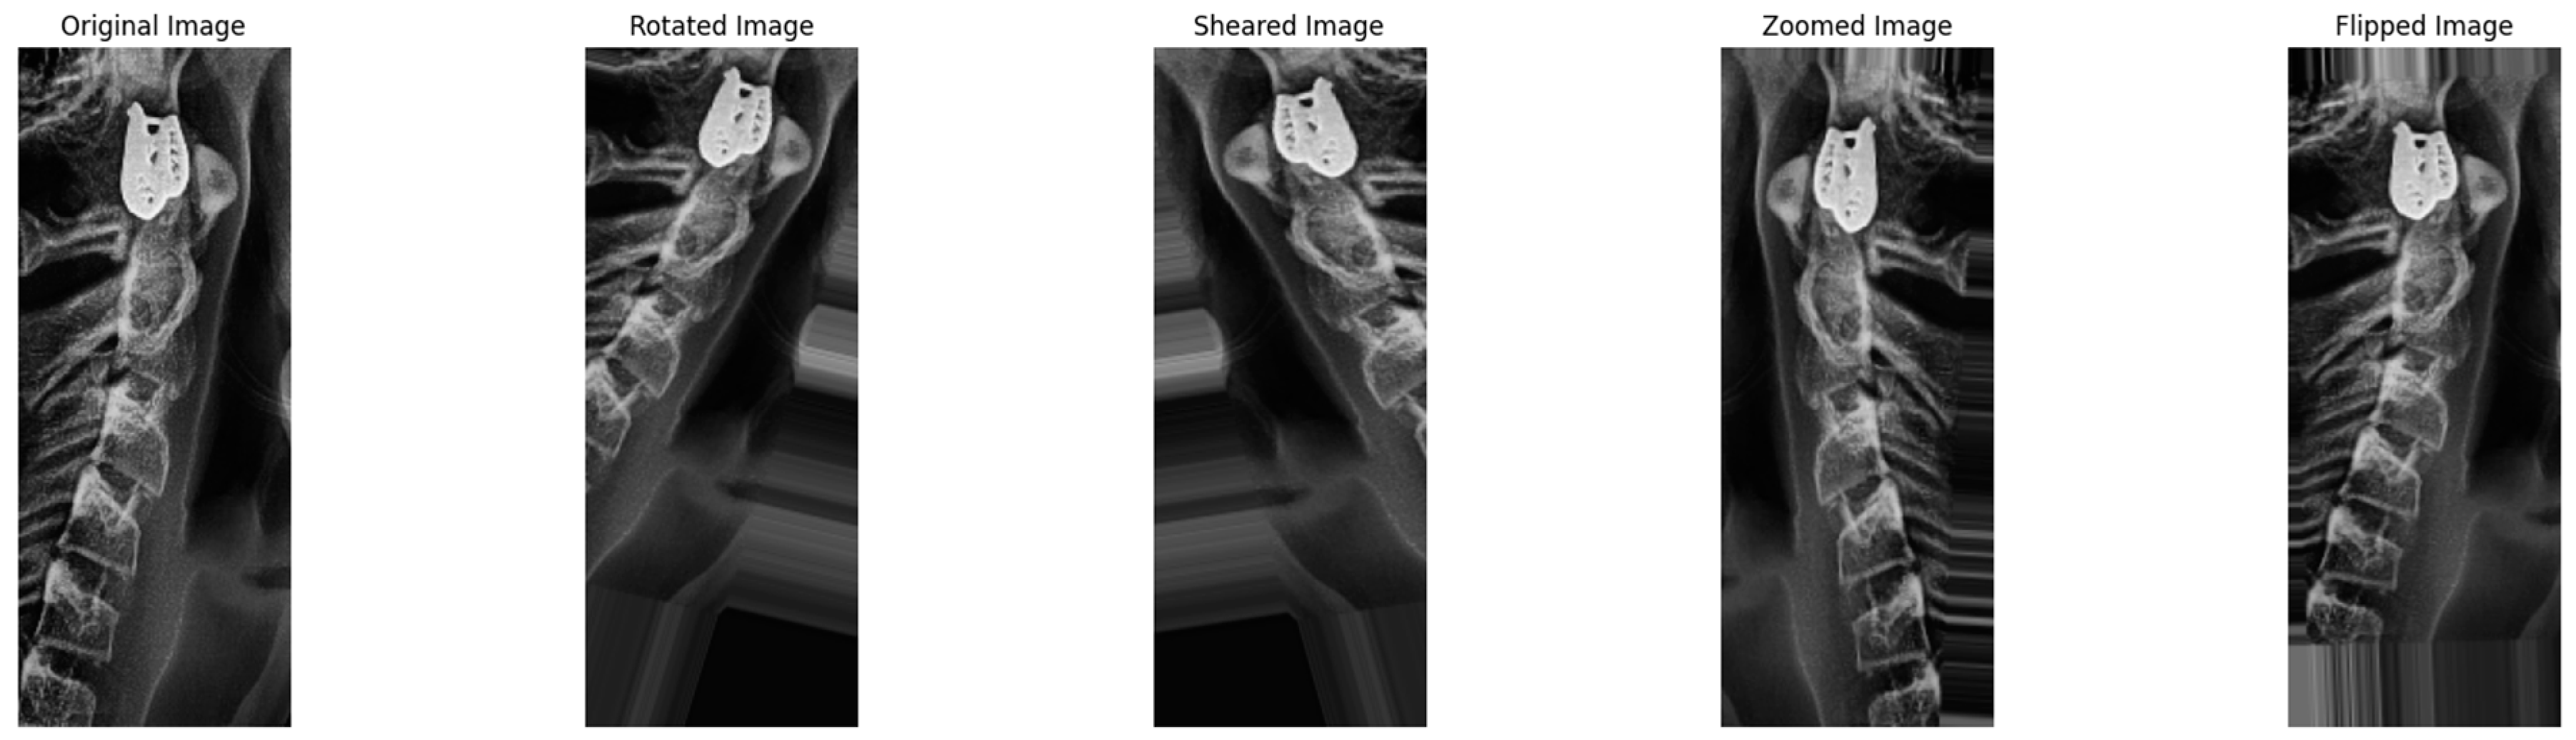

2.3.3. Augmentation Step

- Initialize image data generator with rescaling and light augmentation (zoom, shear, and brightness adjustment) using ImageDataGenerator().

- -

- Create generators for images to be implemented with the augmentation process.